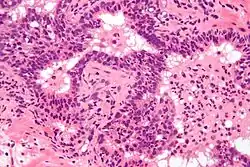

Micrograph showing a neutrophilic infiltration of prostatic glands - the histologic correlate of acute prostatitis. H&E stain.

Antibiotics are the first line of treatment in acute prostatitis. Antibiotics usually resolve acute prostatitis infections in a very short time, however a minimum of two to four weeks of therapy is recommended to eradicate the offending organism completely.[5] Appropriate antibiotics should be used, based on the microbe causing the infection. Some antibiotics have very poor penetration of the prostatic capsule, others, such as ciprofloxacin, trimethoprim/sulfamethoxazole, and tetracyclines such as doxycycline penetrate prostatic tissue well. In acute prostatitis, penetration of the prostate is not as important as for category II because the intense inflammation disrupts the prostate-blood barrier. It is more important to choose a bactericidal antibiotic (kills bacteria, e.g., a fluoroquinolone antibiotic) rather than a bacteriostatic antibiotic (slows bacterial growth, e.g. tetracycline) for acute potentially life-threatening infections.[6]